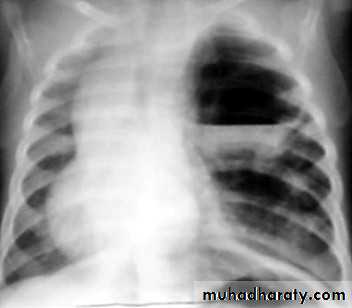

pneumothorax

53.pnuemothorax

54. pneumothorax

55. pneumothorax Right sided aspect